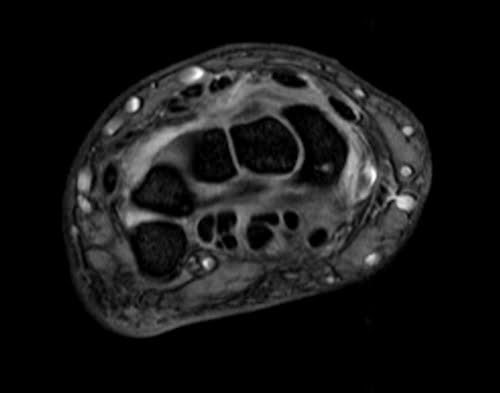

MRI wrist axial medic image 2 - MRI